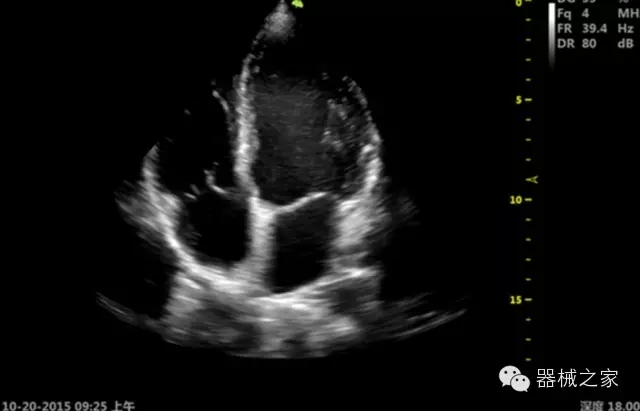

臨床圖片賞析

·心功能綜合指數(shù)(TEI指數(shù)):用于左、右心室整體心臟收縮舒張功能評(píng)估的測(cè)量方法;

·全方位可調(diào)M型:有利于更好的觀察心腔大小及室壁階段性運(yùn)動(dòng)的異常情況;

·組織多普勒成像(TDI):TDI可定量評(píng)價(jià)心肌運(yùn)動(dòng),判斷是否有局部病變,還可評(píng)價(jià)早期的舒張功能;

·MPTEE:經(jīng)食道探頭術(shù)中監(jiān)測(cè),可測(cè)量心臟前負(fù)荷(左室舒張末期大小、右房大小)、心排血量、后負(fù)荷、收縮功能、室壁運(yùn)動(dòng)分析、肝靜脈血流(與中心靜脈壓相關(guān))等,術(shù)后還能及時(shí)評(píng)估手術(shù)效果評(píng)估;